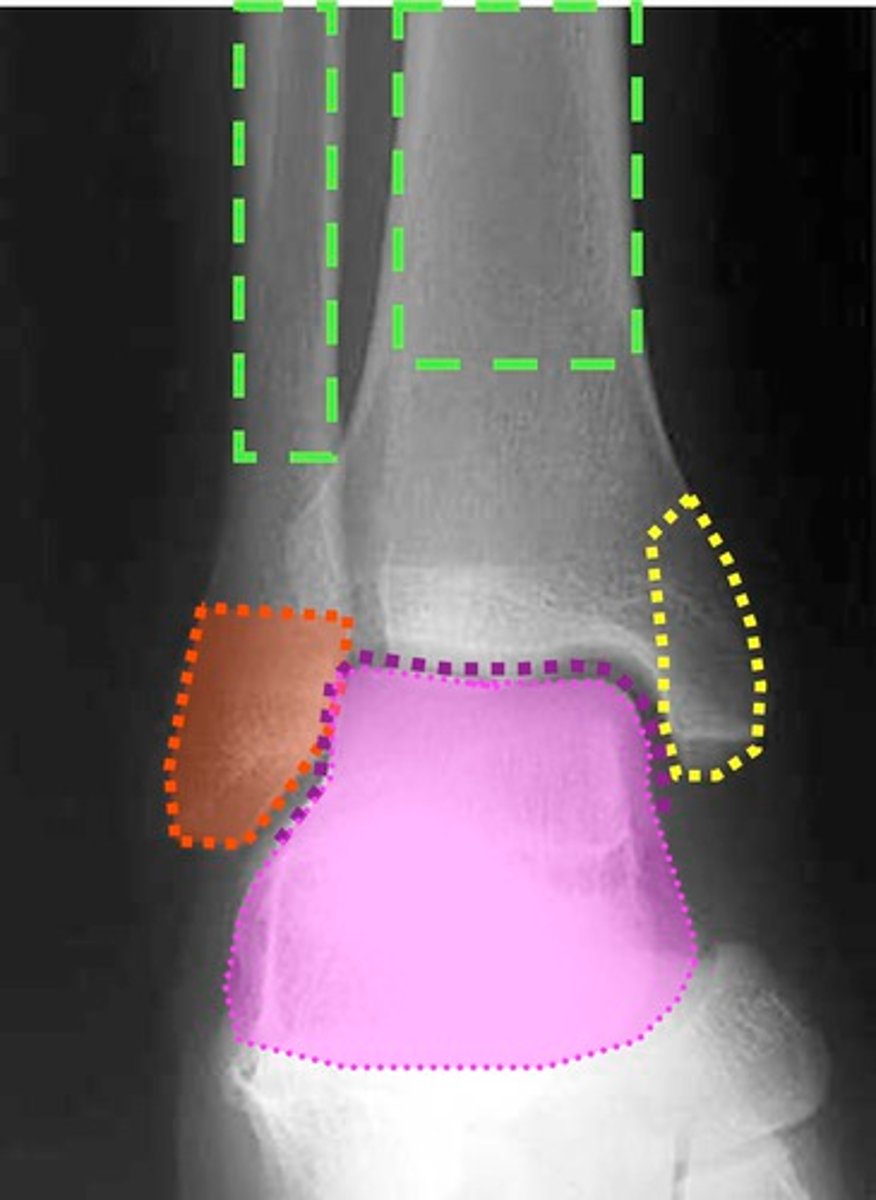

In the talocrural joint, is the talus the convex or concave component?

Talus is CONVEX in the talocrural joint

What is the concave component of the talocrural joint?

The tibia and fibula

What type of joint is the talocrural joint? (specific classification based on shape)

Mortise joint

Why does the deltoid ligament have a lower injury rate than the lateral ankle ligaments? (2 reasons)

Higher strength of deltoid ligaments

Lateral malleolus blocks excessive eversion

The relative inability of the _______ ________ to block the medial side of mortise joint contributes to anterior talofibular ligament sprains.

Medial malleolus